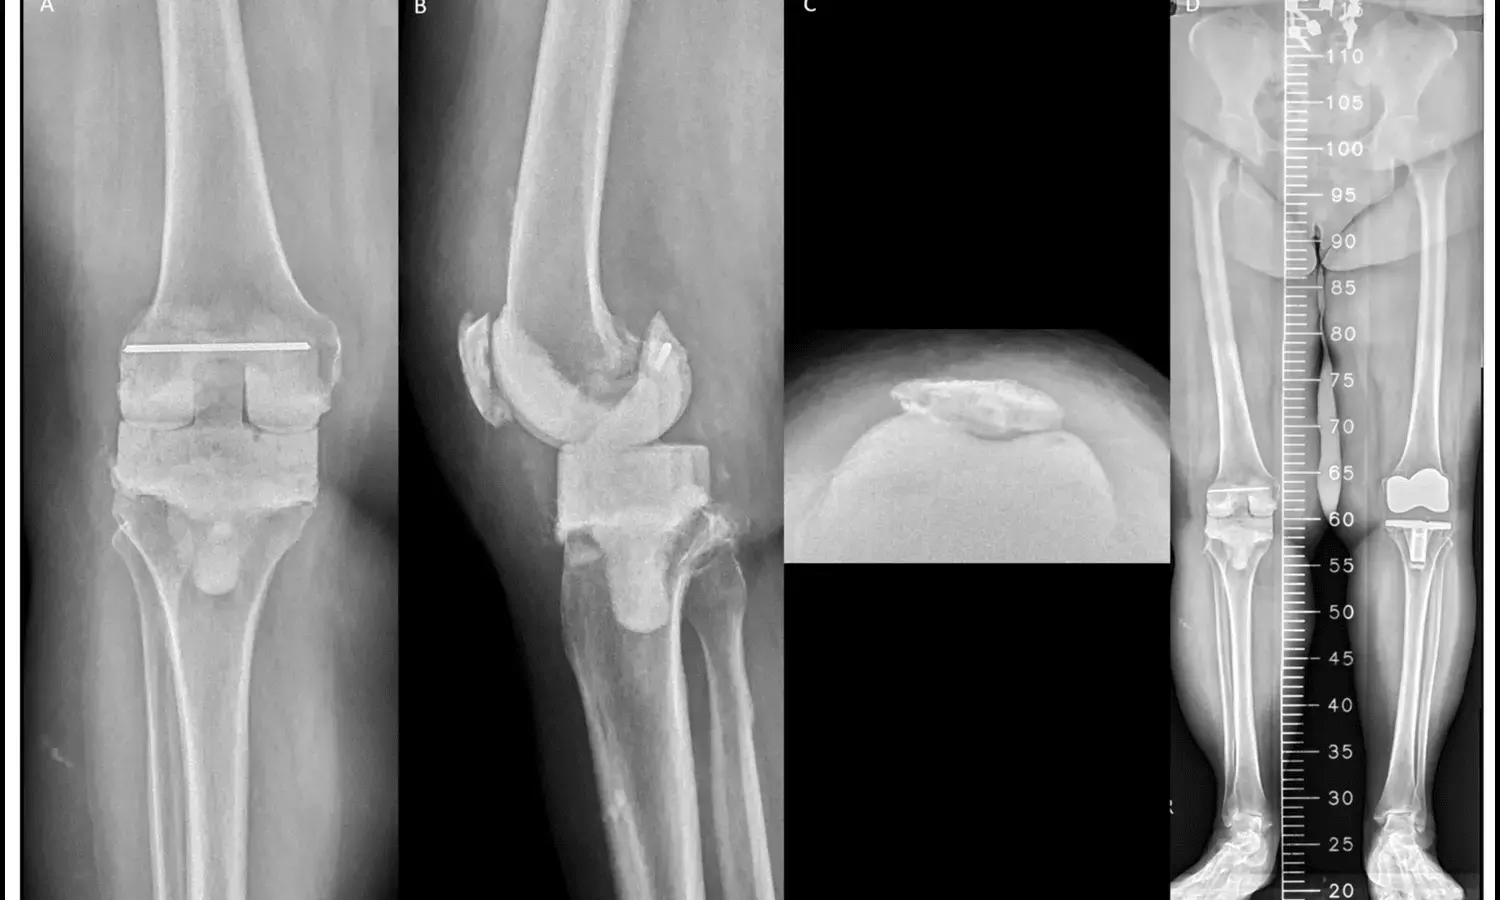

A large register-based study published in BMJ Open has reported that patients with type 2 diabetes undergoing hip or knee replacement surgery face a higher risk of long-term mortality but not an increased risk of reoperation. The research analyzed outcomes from more than 190,000 procedures recorded in Swedish national registers, making it one of the most comprehensive evaluations of diabetes and joint replacement to date. The authors note that while joint replacement is generally effective for improving quality of life in individuals with severe arthritis, the presence of chronic conditions such as diabetes may alter long-term outcomes.

According to the study, type 2 diabetes was linked to a greater likelihood of death after both hip and knee replacement, while the risk of requiring additional surgery remained unchanged compared to patients without diabetes. Short-term adverse events, such as complications occurring soon after surgery, were only minimally affected. The researchers emphasize that other factors—including body mass index and the presence of additional health conditions—were more strongly associated with the need for reoperation and also influenced mortality risk. This suggests that while diabetes itself contributes to poorer survival, the interplay of obesity and comorbid illnesses may be equally or more important in determining surgical outcomes.